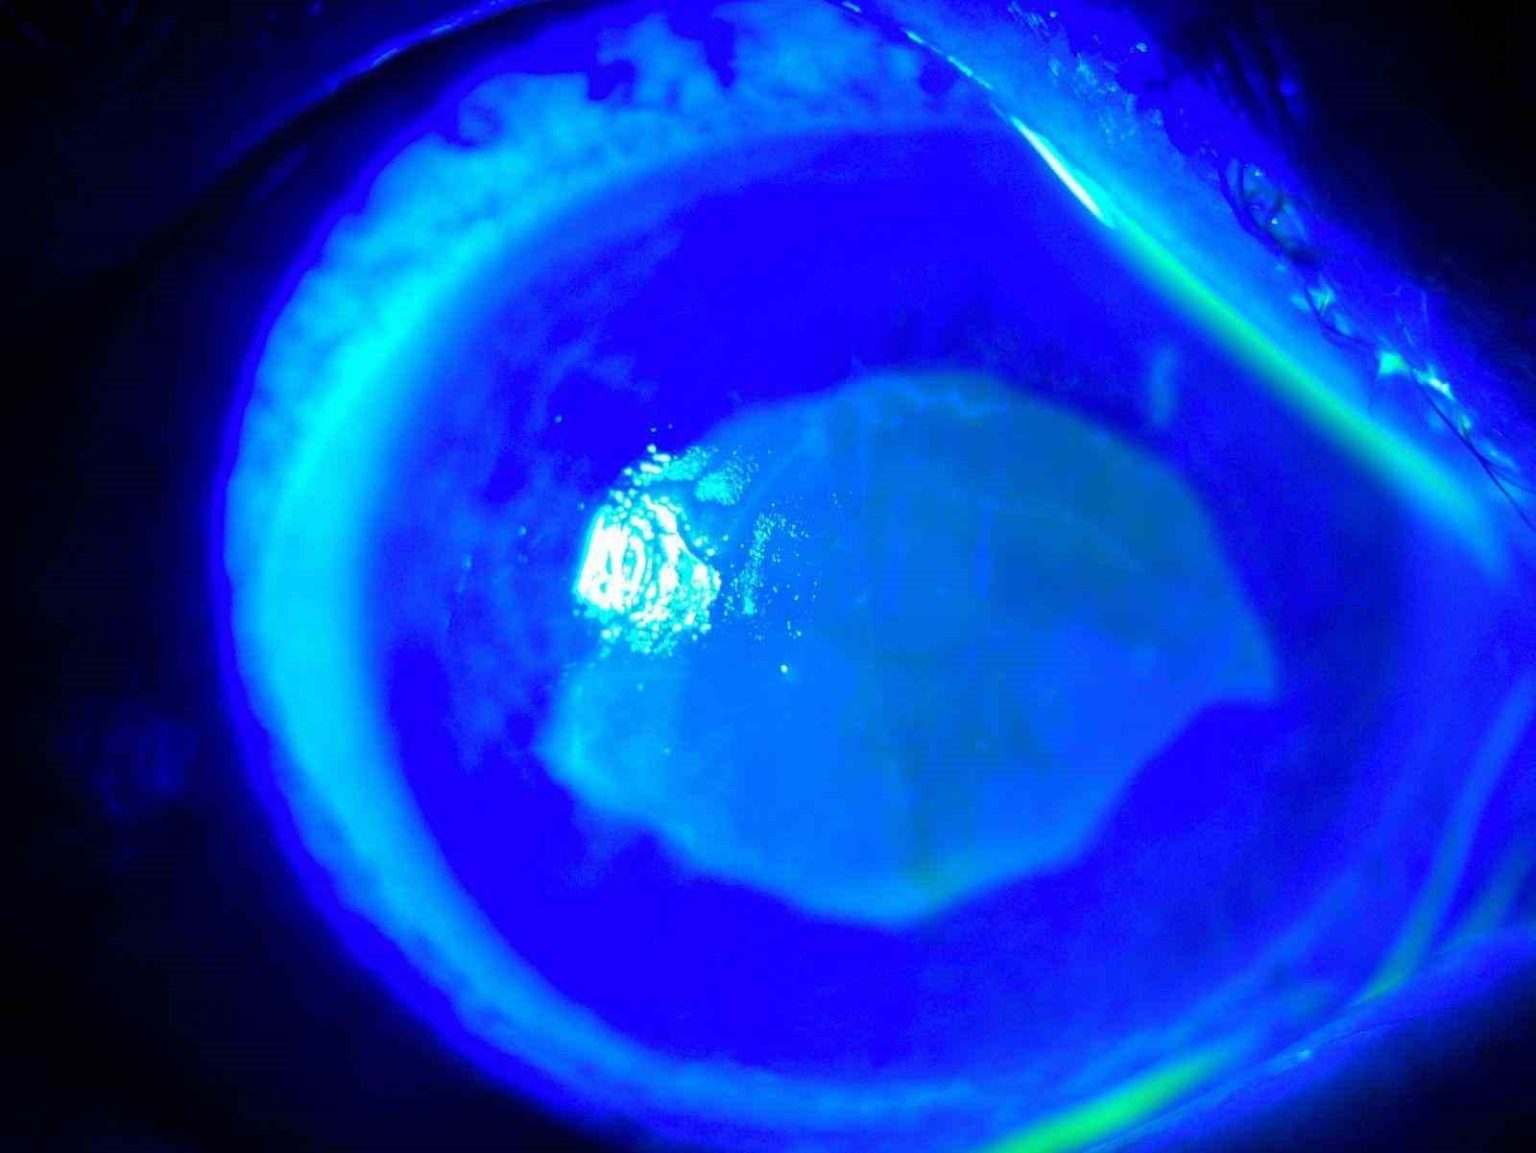

Kocaeli’nde yaşayan 52 yaşında kadın, iddiaya göre uzağı görememesi sebebiyle kullandığı gözlükten kurtulmak için yaklaşık 7 ay önce kırlangıç otunun suyunu gözlerine damlattı ve bir anda göremez hale geldi. Önce gözlerinde yanma, batma hisseden ve sonrasında açamaz hale gelen kadın hemen hastaneye koştu. O dönem Kocaeli’nde çalışan Göz Hastalıkları Uzmanı Doç. Dr. Ömer Faruk Yılmaz ve ekibi hastaya müdahale ederken korneanın en dış katmanı olarak ifade edilen kornea epitelinin zarar gördüğü belirlendi. Göze yabancı cisim, kimyasal madde kaçması ya da enfeksiyon durumlarında gözü temizlemek amacıyla uygulanan göz yıkama tedavisi gerçekleştirildi. Yaklaşık 2 haftalık tedavinin ardından hasta sağlığına kavuştu. Doç. Dr. Yılmaz, hastasının yaşadığı süreç ve tedavisine ilişkin bilgi verdi. Yılmaz, hekim önerisi olmadan herhangi bir ürün kullanılmaması gerektiğine dikkat çekerek önemli uyarılarda bulundu. Öte yandan hastanın göz bebeğinin beyazlığı ve göz akının ise kızardığı hali fotoğraf karesine yansıdı.

Uyguladıkları tedaviye yönelik konuşan Doç. Dr. Yılmaz, “Göz uyuşturucu damla ile hastanın gözünü açtık, muayenemizi yaptık. Kornea epiteli tamamen deforme olmuştu. Her 2 gözünü 25 dakika yıkadık, gerekli tedavi ve damlalara başladık. Yaklaşık 6-7 ay önce oldu, toplam tedavimiz 10 gün- 2 hafta süresince devam etti. Tedavi sonunda 2 gözünde görmesine tamamen ulaştı. Hasta ilk başta çok korkmuştu, 2-3 gün boyunca bayağı sıkıntılar yaşadı. İlk 2 gün hatta ağrıdan, yanmadan, batmadan hasta uyuyamadı, iyileştikten sonra çok mutlu olmuştu. Sosyal medyada özellikle son zamanlarda kırlangıç otu çok yaygınlaşmaya başladı. Literatürü taradığım zaman kırlangıç otunun tarihte birçok hastalıklara; cilt, mide hastalıkları gibi hastalıklara geleneksel olarak kullanıldığını gördüm. Bitkisel ilacın içeriği faydalı olsa bile yüksek doz damlatılması gözümüze zarar verebilir” diye konuştu.

“Kırlangıç otu kullandı, hastamız göremez hale geldi eğer tedavi edilmeseydi sonucun ne olacağını bilemiyoruz fakat tedavi sonucunda hastamız iyileşti. Gözlerinin fotoğrafını çektirdim, kırlangıç otunun geçişini gösterdik. Tedavi edilmediği zaman göz içinde belki de körlüğe ulaşabilecek şekilde istenmeyen yan etkilere yol açabilir. Yüzlerce farklı ot olabilir, yanlışlıkla faydalı bir ot damlatacağız diye zararlı bir otu damlatabiliriz. Göze direkt damlatılması steril değildir, göze zarar verebilir, enfeksiyon oluşturabilir. Faydalı bile olsa Sağlık Bakanlığı ruhsat vermeden, ilaç formatına dönüştürmeden, uygun dozajlar ayarlanmadan ve göz hekiminin önerisi olmadan göze herhangi bir bitkisel ilaç damlatılmasını önermiyoruz.”